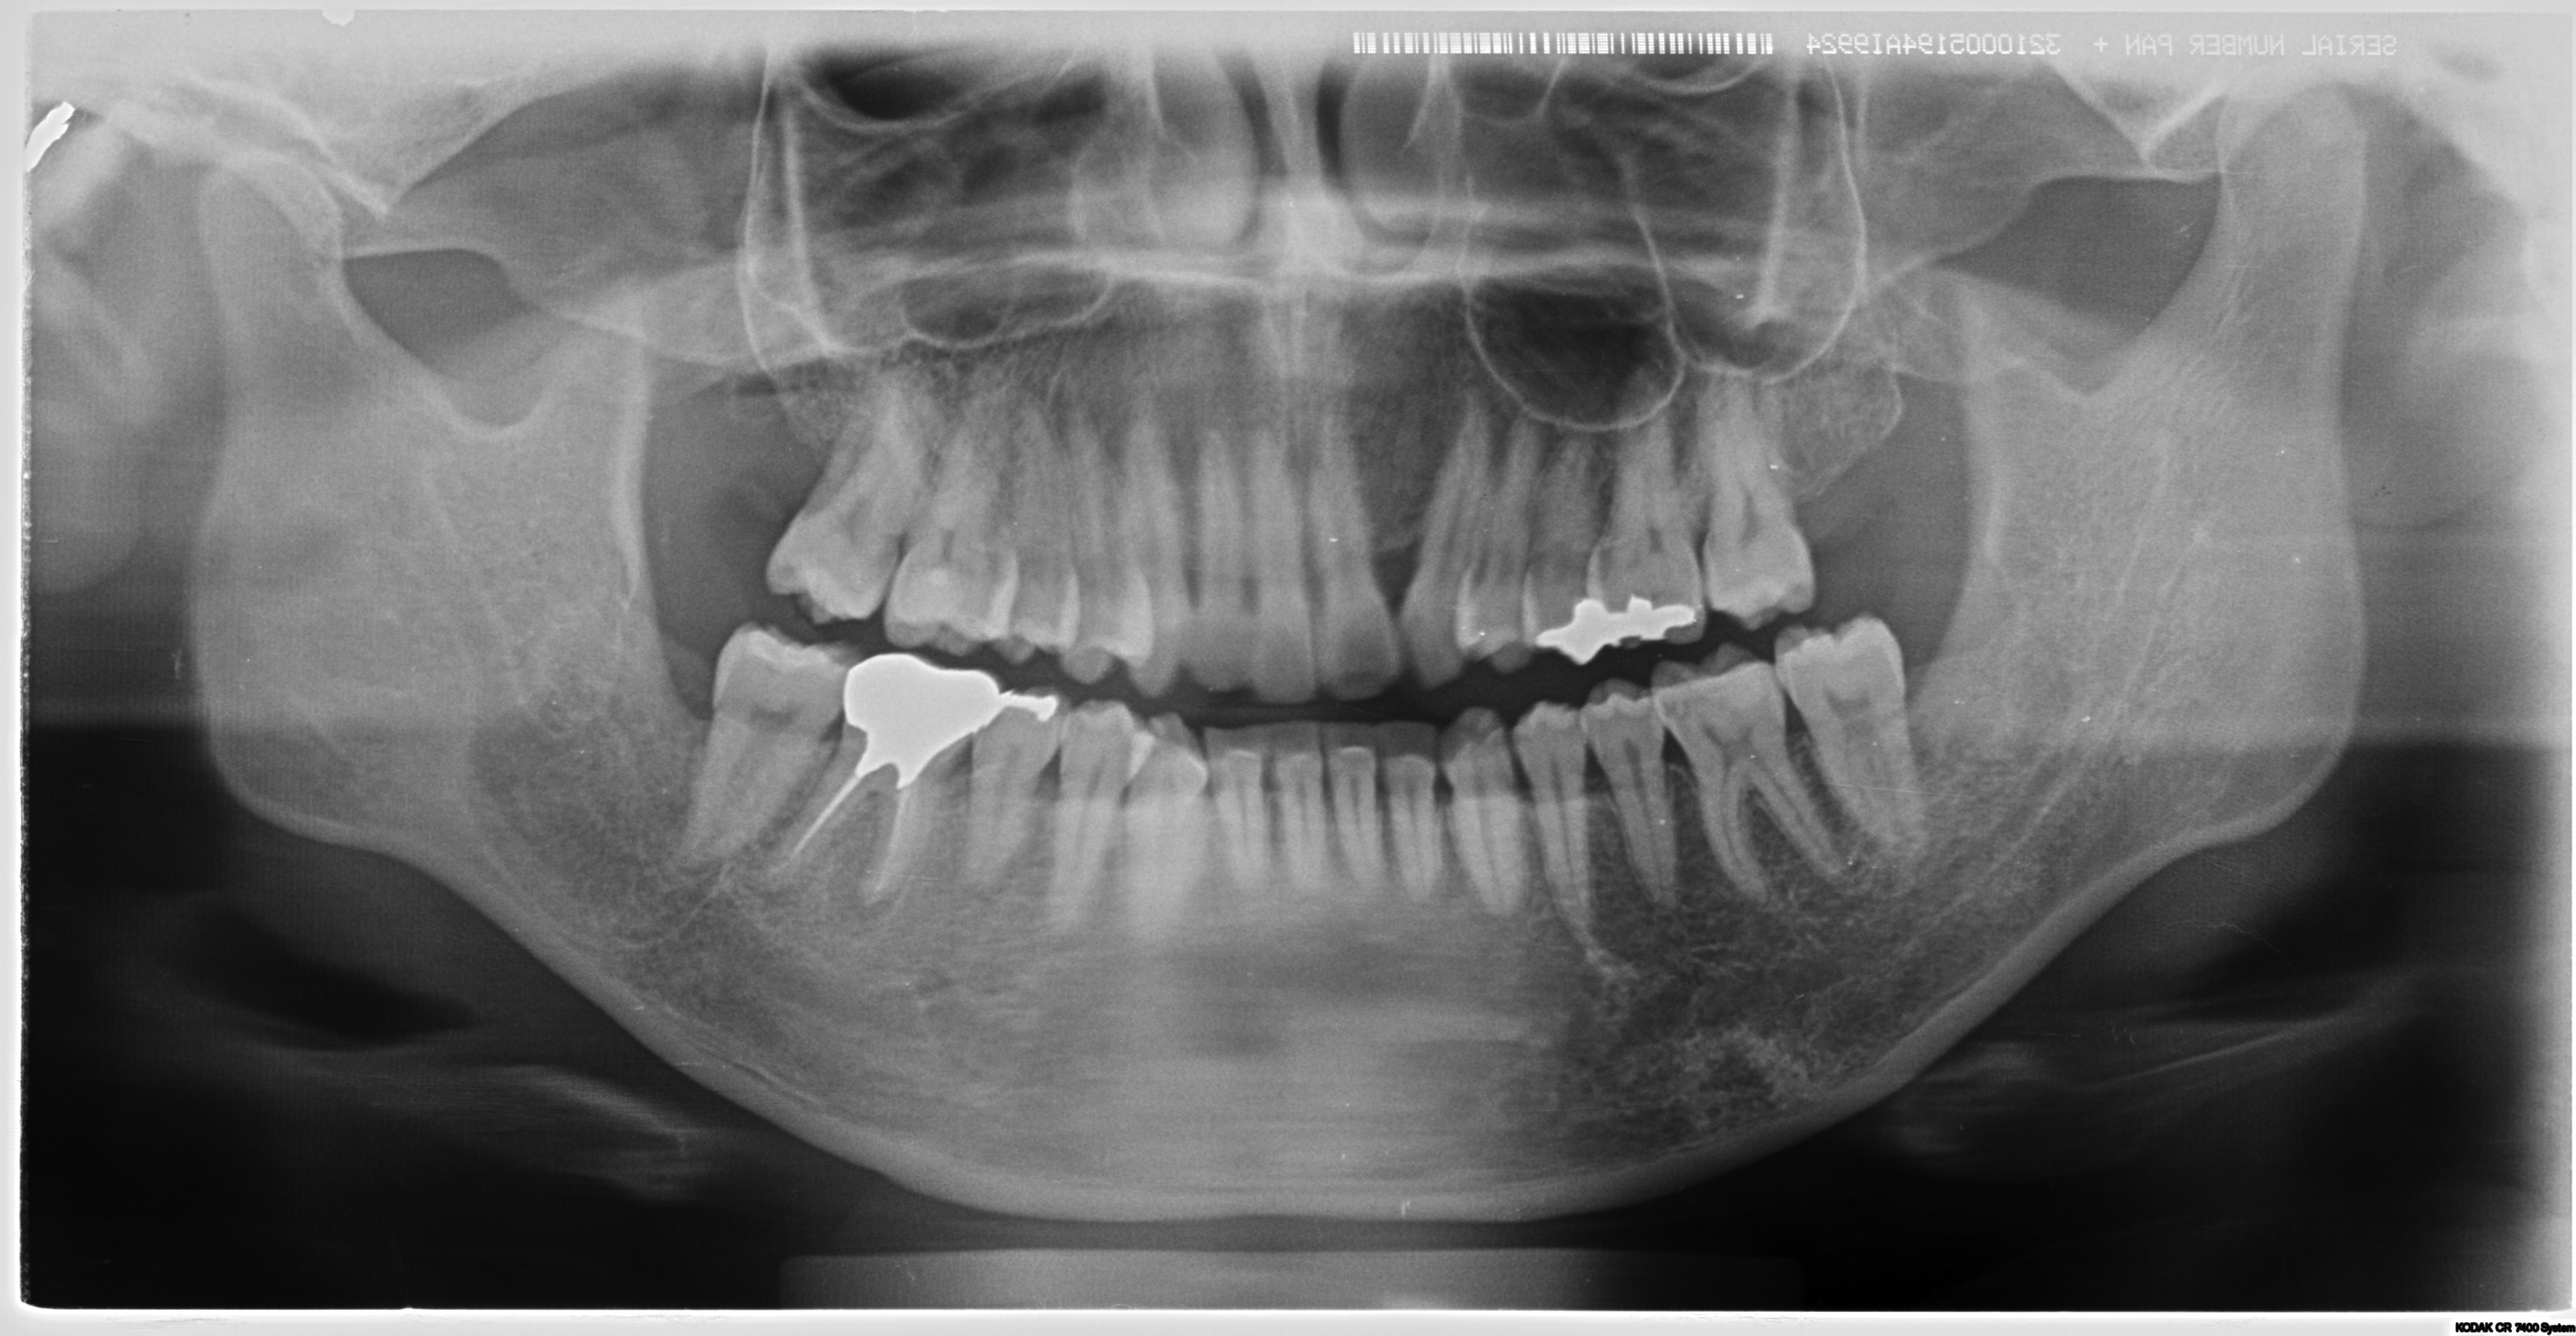

某大学病院で全身麻酔での嚢胞摘出及び右下7番の抜歯を予定されていた方の治療経過

<親知らずなどの抜歯に関して>

多くの方が経過観察になっていることが多いのが親知らずでしょう。一度腫れたりすると抜歯をしようかなと考えて歯科医院に行くケースもありますが。

完全に埋まっているケースは放置されることが多いです。(自覚症状がないため)

またそうした難抜歯は通常開業医では行わないケースが多いです。

しかし当クリニックではそうした難抜歯を積極的に行っております。

理由は簡単で症状が「歯列の乱れ」「歯周病の悪化」「口臭の原因」「手前の歯を虫歯にしてしまう」からです。

完全に埋伏しているように見えても、抜歯した時には歯茎の中にあるにもかかわらず歯石まみれの汚い状態で抜歯できるケースはザラにあります。

ご本人が気が付かないだけで、埋まっている歯ぐきから膿が常に出ている方もたくさんいらっしゃいます。(特に40代以降の方に多い)

こうした方々は常に口臭がしたり、体調によって歯茎が腫れたりしています。

他の開業医で「大学病院などでの抜歯を勧められた」などの困難症例もご相談ください。

大学病院では全身麻酔などを行い抜歯するケースも多いですが。

麻酔科医としての見解からすれば、わざわざ全身麻酔を行い(呼吸を停止させ、挿管し人工呼吸で管理することです)抜歯を行うケースは相当のリスクを伴います。

可能な限り外科処置に関しては局所麻酔で抜歯を行う事が侵襲は少ないと考えます。

そのため原則局所麻酔下(部分だけの麻酔)での抜歯を行っております。

必要な症例に関しては大学病院等に紹介をいたします。